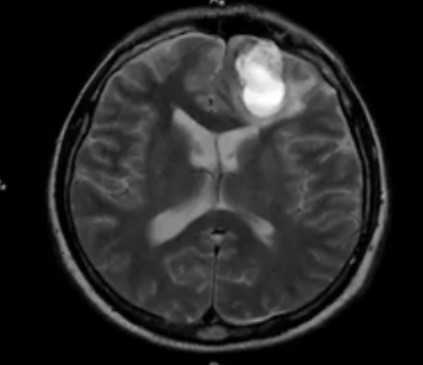

Внутримозговая гематома травматического характера на МР-снимке